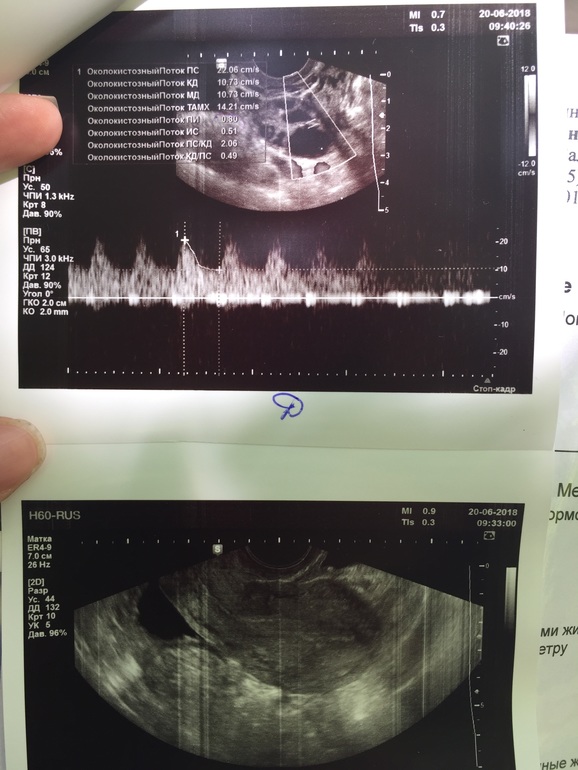

Хожу в основном в одно и тоже место, там аппарат хороший и врач.. но попала сегодня на другого врача, и она не знает!! Говорит, что О была, потому что у правого Я есть жидкость, но ЖТ не видит 😄🤷♀️ возможно типа ещё не образовалось, или не видно из-за еще одного ДФ 17мм.. или это вообще тот же фолликул, что и на 14дц был🤦🏼♀️ Та же история с ЛЯ.. но там вроде все-таки ЖТ есть, и то не факт😂

Вот теперь сижу, гадаю...) жду протокол)) по сути.. от укола 10000 фолликулы же не могли остановиться/уменьшиться.. они либо в кисту бы уже ушли, либо лопнули. Но кист нет, и нет ЖТ.. есть 2 ДФ в каждом Я. Узист даже не стала писать в заключении.